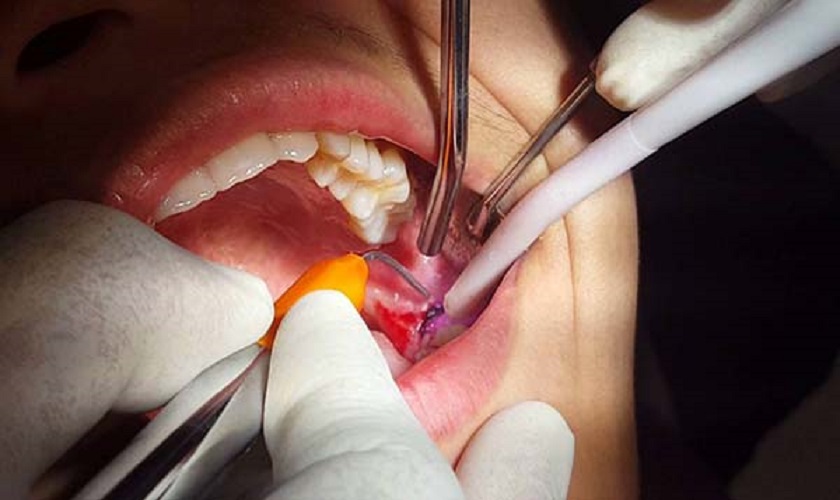

Nhổ răng số 8 đòi hỏi bác sĩ có trình độ chuyên môn cao, tay nghề tốt vì rất dễ chạm vào dây thần kinh, làm tổn thương nướu và các răng kế cận, gây ra nhiều biến chứng phức tạp.

Trước khi nhổ răng số 8, bạn cần tiến hành chụp X – quang, xét nghiệm máu,… để bác sĩ nắm được mức độ phức tạp, tình trạng răng một cách cụ thể cũng như tránh các rủi ro do các vấn đề về đông máu,…

Ngoài ra, công nghệ, máy móc hỗ trợ, lượng thuốc tê nhiều hơn trong trường hợp răng mọc ngầm cũng sẽ đẩy giá nhổ răng khôn lên cao hơn tương đối nhiều so với răng bình thường.